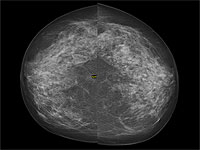

Отсутствие первой маммографии повышает риск смертности от рака молочной железы

Wikipedia.org. Фото: Nevit Dilmen

Женщины, которые не проходят первую маммографию, сталкиваются с повышенным риском обнаружения рака молочной железы на поздней стадии и более высокой вероятностью летального исхода. К такому выводу пришли ученые Каролинского института, результаты их исследования опубликованы в научном журнале BMJ.